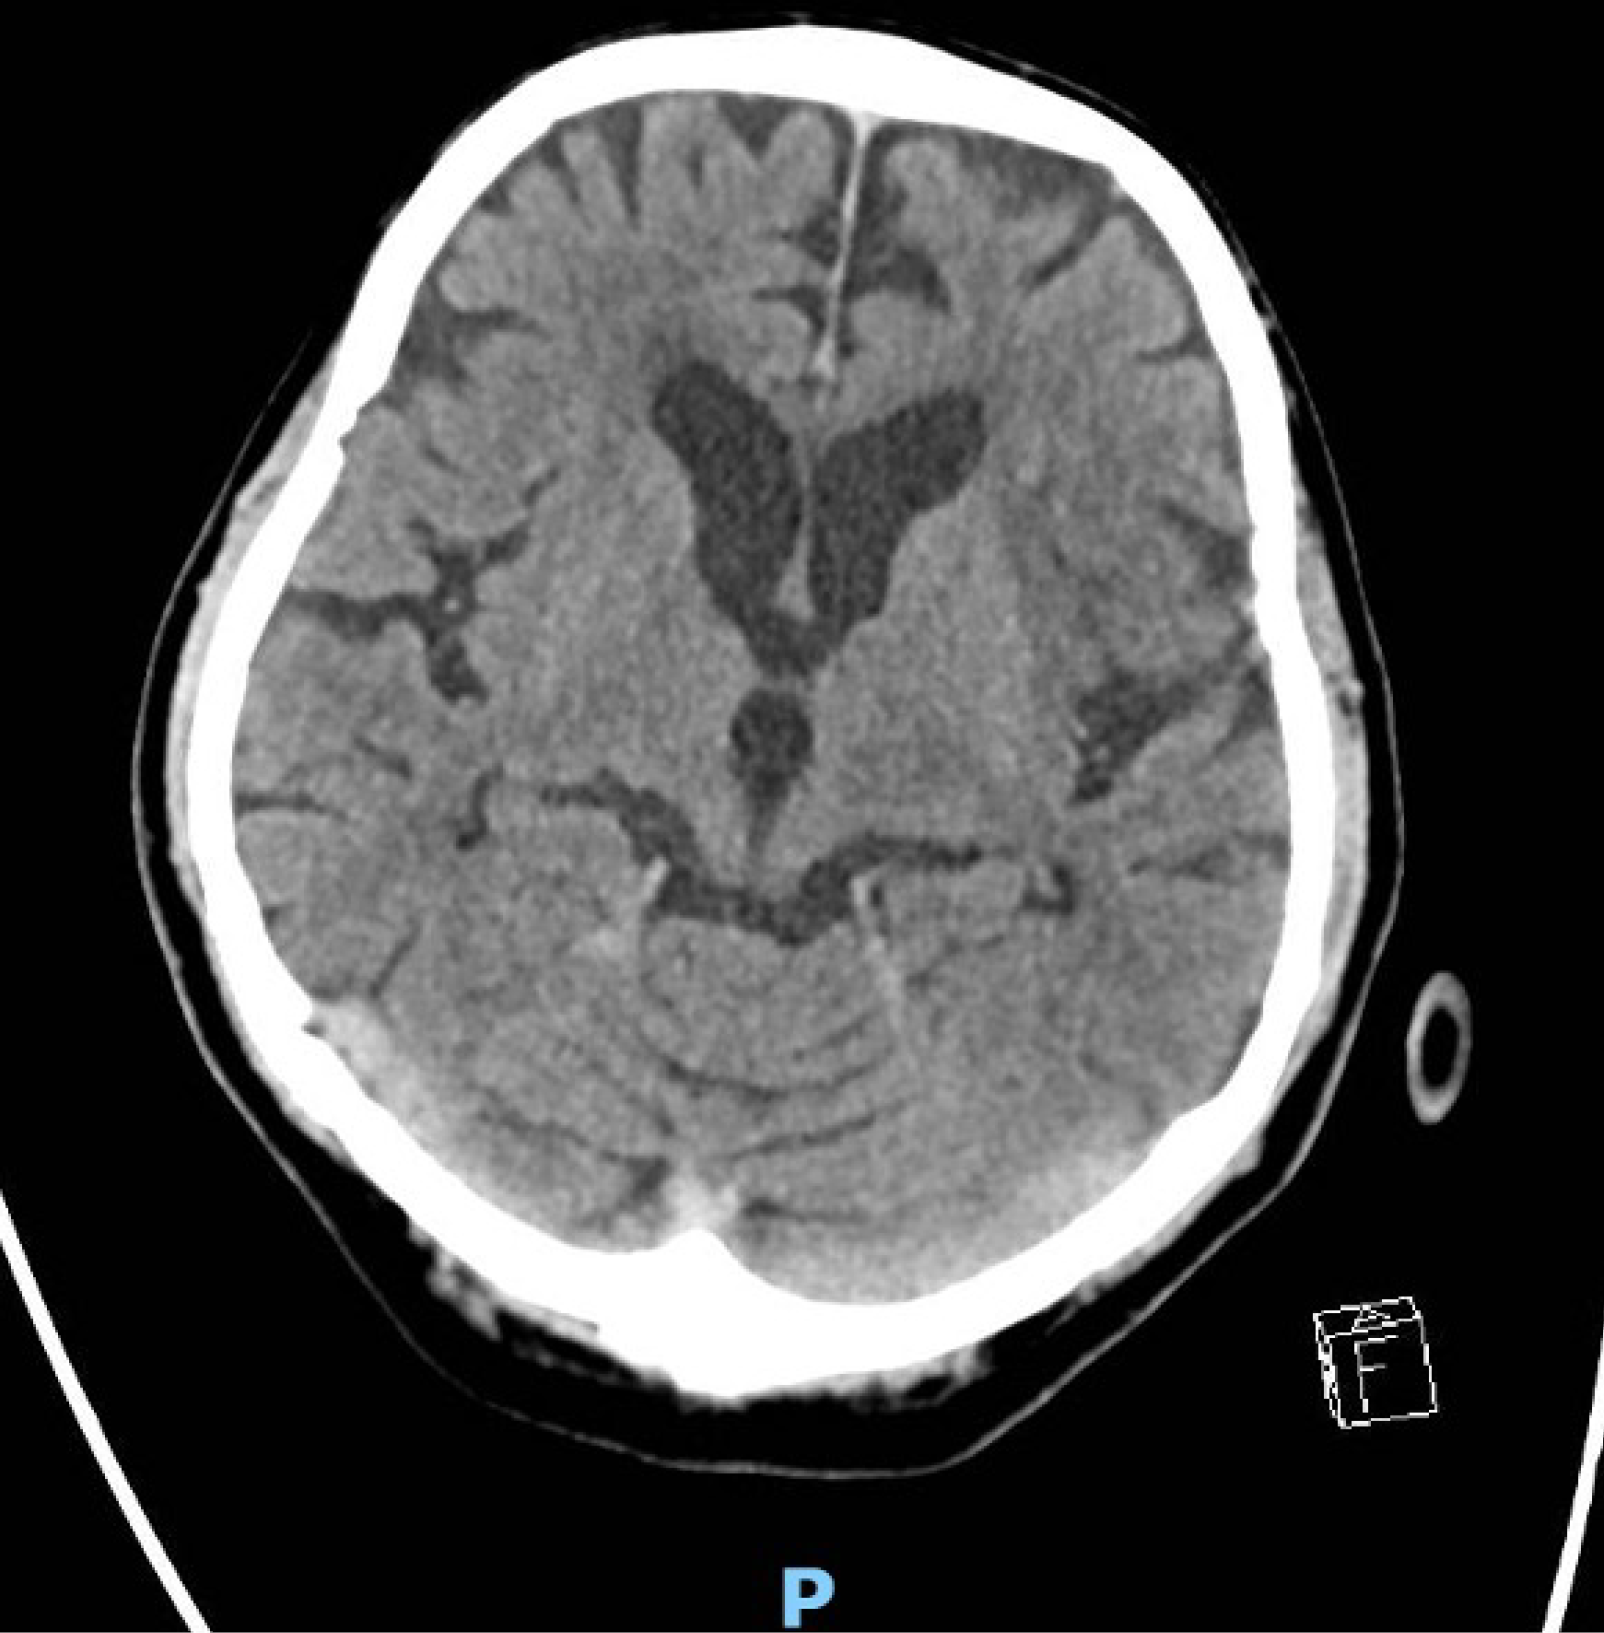

Figure 6 Repeat computed tomography brain of the patient, showing loss of grey-white matter differentiation in the left insula and left M2 region suspicious for an acute left middle cerebral artery territorial infarct.

There is no evidence of haemorrhagic conversion or midline shift.